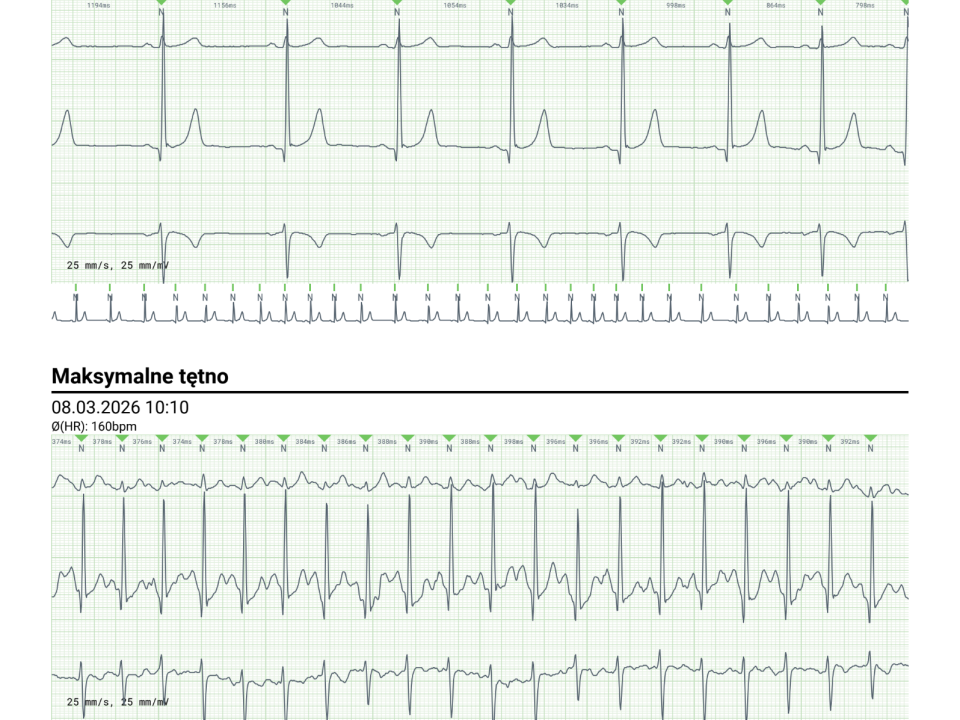

Serce – możliwe zaburzenia rytmu

Choć amiodaron jest lekiem przeciwarytmicznym, może w rzadkich przypadkach powodować zaburzenia rytmu serca lub nadmierne zwolnienie tętna.

Dlatego ważne są regularne kontrole EKG.